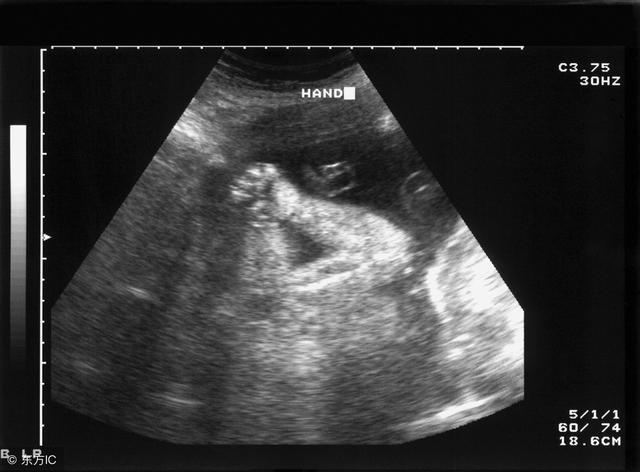

股骨长是大腿骨长度,是医生利用B超(或彩超)给孕妇作孕期检查时,用它来观察胎儿发育的情况常用的指标。

2、根据胎儿双顶径和股骨长计算孕周,1个具体实例,附胎儿发育情况

小雪怀孕几个月了,但是她自己也忘了末次月经的的时间是多少,不知道自己是多少周了,就去做了一次B超,想根据B超的结果来判断怀孕的周数。她做完后就把数据发给了我,上面写着“双顶径4.4厘米,股骨长3.2厘米”,问我这是多少周了?

我只会用双顶径、股骨长标准对照表来给帮她计算,如果医生的话,还会有更准确的方法。因为孕周的计算是一个非常综合的信息,单靠这两个数据是很难算准的。但是估算一下是可以的,毕竟预产期也是一个大概日期,大概知道自己怀孕的日期也比不知道强。

胎儿双顶径4.4厘米,股骨长3.2厘米,胎儿大概多少周了?

根据双顶径、股骨长标准对照表查询,

双顶径4.4厘米介于18周和19周之间,

股骨长3.2厘米介于19周和20周之间。

综合来看,胎儿大概是19周。